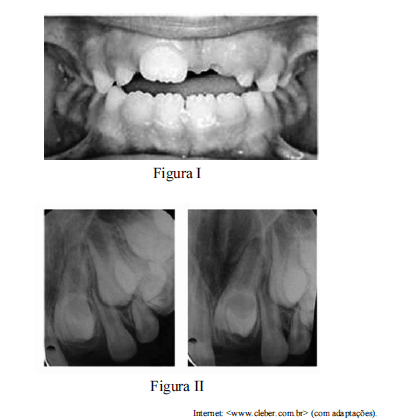

Uma paciente de seis anos de idade foi levada a um consultório odontológico para a realização de uma consulta de rotina. Ao examinar a arcada dentária da criança, o cirurgião-dentista observou que, apesar de ter havido a erupção do dente 11, ainda não havia ocorrido a erupção do elemento 21, conforme mostrado na figura I. Após a realização de radiografia da região periapical, constatou-se a presença de dente supranumerário impedindo a erupção do elemento 21, conforme apresentado na figura II, motivo pelo qual o cirurgião-dentista recomendou a remoção cirúrgica do dente supranumerário.

Tendo como referência as imagens apresentadas, julgue os itens subsecutivos, relativos ao caso clínico descrito.

O momento ideal para a realização da remoção cirúrgica em casos de hiperdontia como o apresentado na situação hipotética é definido após avaliação de fatores como a idade do paciente, sua capacidade de colaboração e o estágio de seu desenvolvimento dental.